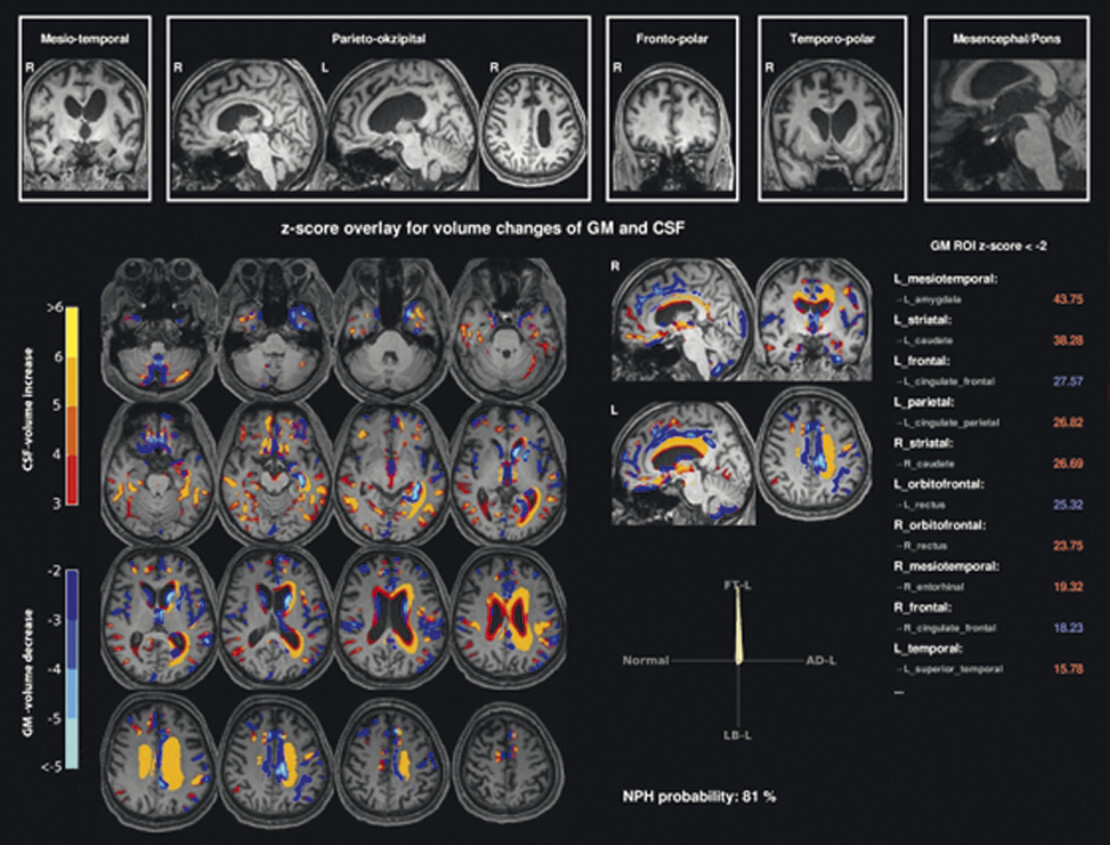

- Speziell zur Beurteilung fokaler Atrophien ist die Anfertigung einer T1w 3-D-Sequenz obligatorisch. Auf Basis dieser T1w 3-D-Sequenz können zwischenzeitlich kommerziell erhältliche, automatisierte volumetrische Analyseverfahren inklusive künstlicher Intelligenzalgorithmen die Diagnose bezüglich abnormer Hirn- und Liquorvolumina unterstützen [4].

Abb. 69.7 Parkinson-Syndrome: Differenzialdiagnose Multisystematrophie vom zerebellären Prädominanztyp.

67-jährige Patientin mit über Jahre progredienter Verschlechterung des Gleichgewichts, Schluckstörungen und Sprechstörungen. In der T1w 3-D-Sequenz zeigt sich eine ausgeprägte Atrophie des Pons (a, Pfeil), der mittleren Kleinhirnstiele (b, Pfeile) und des Kleinhirns. Diese Veränderungen werden durch die Ganzhirnvolumetrie bestätigt (c): Anomale Regionen der grauen Substanz (mindestens 2 Standardabweichungen unter dem vergleichbaren Volumen des gesunden alters- und geschlechtsgematchten Normkollektivs) sind blau überlagert. Anomale Liquorvolumina (mindestens 2 Standardabweichungen über dem vergleichbaren Volumen des gesunden alters- und geschlechtsgematchten Normkollektivs) sind als rote bis gelbe Überlagerungen auf das individuelle Patientengehirn projiziert. MRT-morphologisch lässt sich somit die Verdachtsdiagnose Multisystematrophie vom zerebellären Prädominanztyp bestätigen.

a Sagittale T1w 3-D-MRT-Sequenz.

b Axiale T1w 3-D-MRT-Sequenz.

c Voxel- und regionenbasierte Analyse.